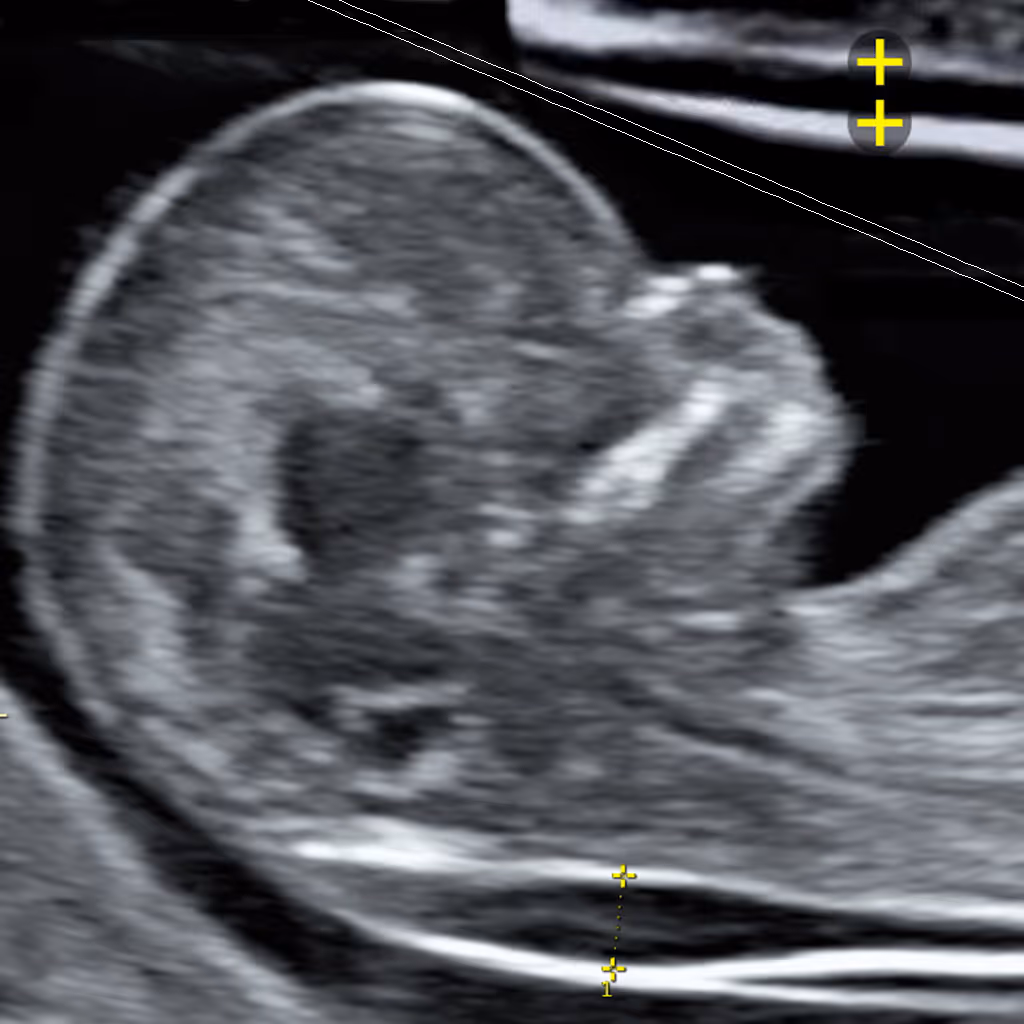

The NT measurement technique was developed by Prof Kypros Nicolaides and the Fetal Medicine Foundation (FMF) in the UK, setting the international standard for accurate and consistent NT assessment. According to the FMF protocol the baby is imaged in a true mid-sagittal plane showing the facial profile. NT is measured as the maximum thickness of the fluid space between the skin and soft tissue over the neck, with the fetus in a neutral position and the image magnified so the head and upper chest fill the screen. Callipers are placed on the inner borders of the echogenic lines defining the NT. To ensure accuracy, three separate measurements are recommended, and the largest valid reading is recorded.